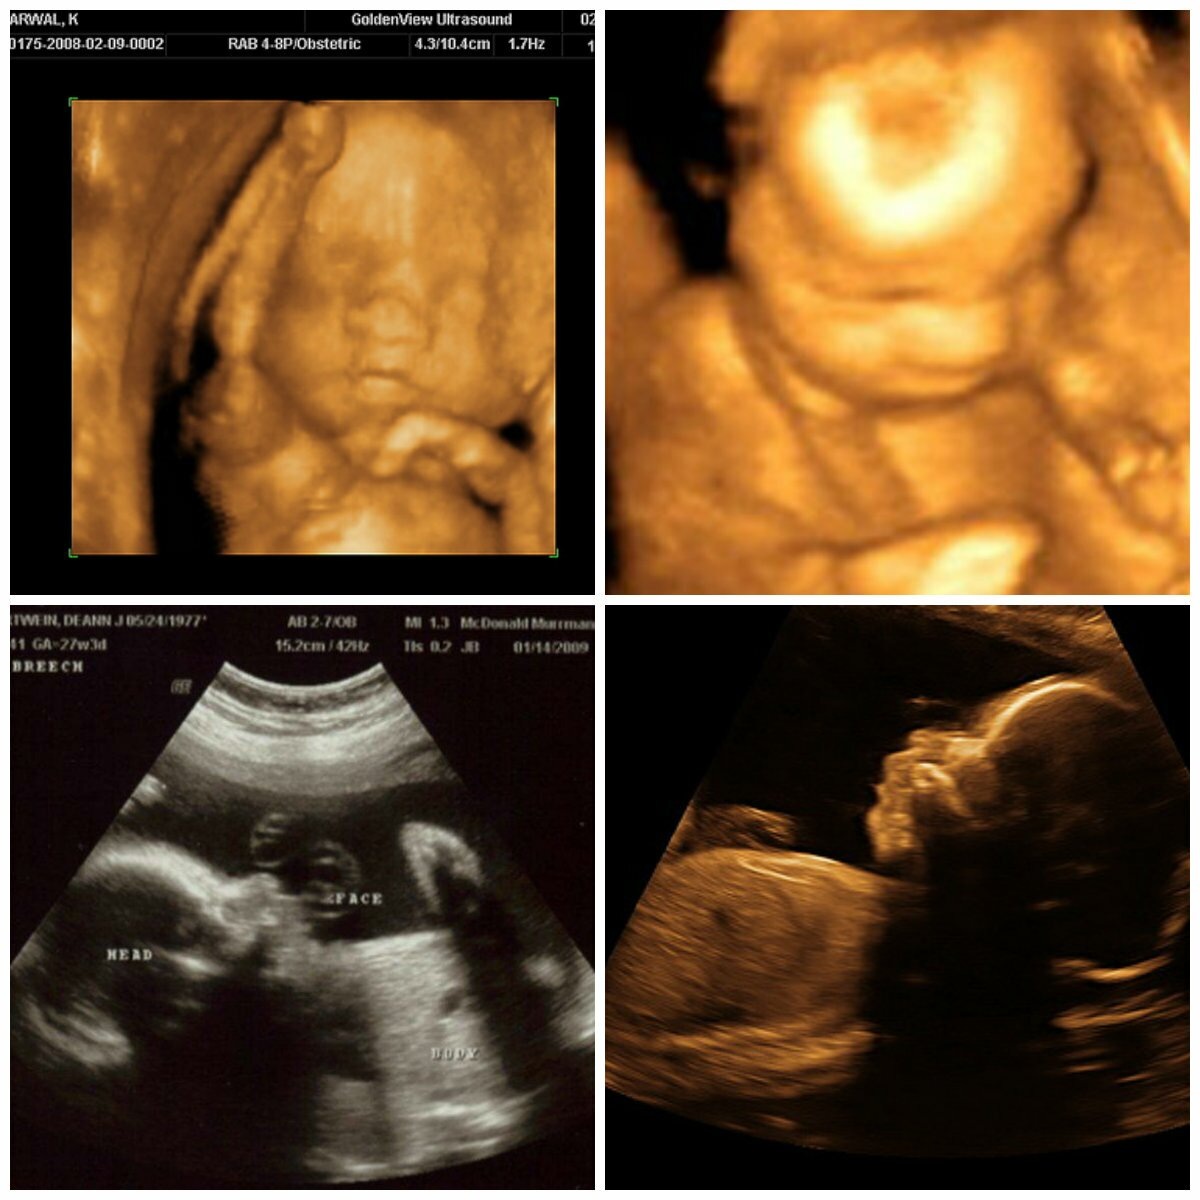

По первому пункту все отлично! Все кисточки рассосались, вопросов к развитию и состоянию моей крохи нет. Активная хорошенькая девочка весом 730 гр))) Примерно такая:

Из открытых источников

Почему я волновалась за пол крохи? Настолько привыкла, что у меня под сердцем девочка, что очень боялась ошибки. Тогда сказали об этом не совсем уверенно, поэтому сомнения меня мучали. УЗИ-изображение было не очень четким и я тоже могла ошибиться, когда увидела пол, да я ж и не специалист. Сегодня все было чётко и ярко. Теперь успокоилась.